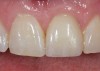

Achieving outstanding esthetics with implant dentistry is a reality (Figure 11 and Figure 12). Restorative efforts require disciplined steps to attain predictable results. To paraphrase my mentor, Cary Shapoff, DDS, renowned for his knowledge of periodontal disease treatment, bone grafting procedures, and dental implant surgery, implant esthetics is a series of well-planned, well-executed small steps that add up to a successfully restored fixture.